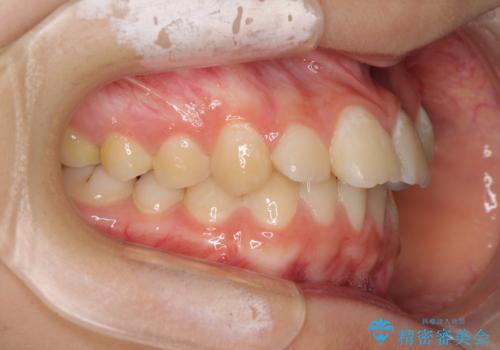

目立つ八重歯を治したい インビザラインによる矯正治療

- 目立つ八重歯を改善したいとのことで来院された患者様です。

奥歯の咬み合わせは左右とも理想的なものでしたが、下顎前歯が1本欠損しているため、上下のバランスを保つことが難しい歯列でした。

唇を閉じたときに上顎前歯が下顎の唇に乗っかる印象があったため、八重歯の後方にある小臼歯を1本抜歯することとしました。

変則的な抜歯となるため、臼歯の咬合が理想的でなくなることが懸念されますが、インビザラインにて矯正治療を行うこととしました。